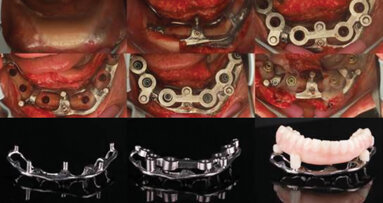

Case presentation

The following case exhibits the features and benefits of utilising Grammetry in combination with innovative screw technology. The 63-year-old male patient with a non-contributory medical history presented with failing dentition in both arches. Diagnostic records were collected, including full-mouth digital radiographs (RVG 6200, Carestream Dental; Fig. 11a), intra-oral scans (Medit i700 wireless; Figs. 11b & c), a large field of view CBCT scan (Carestream 9600; Fig. 11d), and intra-oral and extra-oral photographs (Fig. 11e). The mandible contained an impacted canine as well as several mobile and painful teeth. The maxilla was in a similar condition, having deteriorating, painfully mobile teeth, as well as extensive caries. While the bone loss was significant in the mandible, the vertical dimension of occlusion (VDO) allowed for both arches to be treated with an FP-1 prosthesis.

The collected data, along with preliminary plans for potential implant receptor sites (Blue Sky Plan, Blue Sky Bio), was submitted to the laboratory (ROE Dental Laboratory) for review. The 3D data from the CBCT scan was then merged with the IOS data set to aid in determining a restoratively driven solution for both arches. The laboratory then designed provisional full-arch screw-retained restorations utilising CAD software at the designated VDO required for the prostheses. The desired tooth position as visualised with the 3D reconstructed volume of bone helped to determine the most favourable implant receptor sites. A virtual remote planning session was held with the laboratory to finalise the full-template guided surgical plan (CHROME GuidedSMILE, ROE Dental Laboratory), which incorporated a 2 mm increase in the VDO, and the case was sent for production. The CHROME GuidedSMILE protocol consists of several component parts, which provide a stackable solution with metallic scaffolding to control the bone reduction, the preparation of the osteotomies, full-template guidance of the implants into the bone, control of implant depth, trajectory and rotational indexing, the positioning of the MUAs and the delivery of the provisional restorations.1

The surgery for both arches was completed in a single visit under intravenous sedation. All the remaining teeth were extracted, and selected teeth were then pulverised utilising the Smart Dentin Grinder (KometaBio) and sterilised to be used as autografting bone substitute2 (Fig. 12).

A biologically driven drilling system for anatomical alveolar sculpting (Universal Shapers) was employed (Fig. 13). The alveolar bone was scalloped utilising the diamond shaper drills for both implant and pontic sites to promote emergence profiles for enhanced aesthetics according to the basic tooth size requirements assessed from the initial data collection. The surgery was uneventful except for a mild complication during the extraction of the impacted mandibular canine. Implant stability was measured with resonance frequency analysis (implant stability quotient) to validate loading. MUAs were secured to each implant based on the rotational positions predetermined by the surgical planning. Deficient sites and residual tooth sockets were then grafted with the ground dentine autograft, covered with platelet-rich fibrin membranes and sutured around the healing abutments. Provisional restorations were fabricated using the C2F protocol (Figs. 14a & b).4 After customisation and polishing, the provisional restorations were inserted and allowed to heal (Fig. 14c–e).